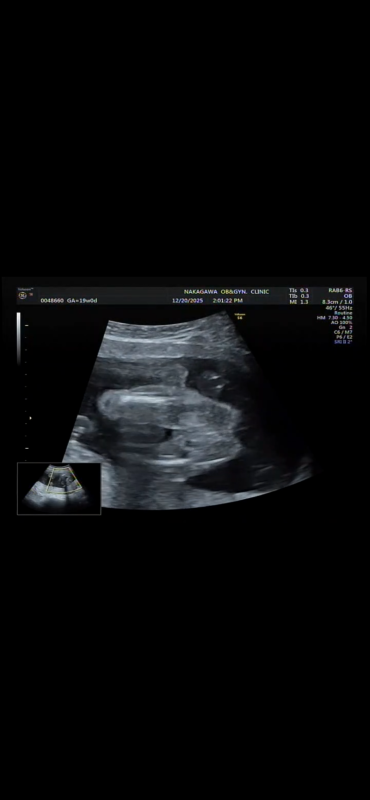

19週になりましたが、まだ性別がわかりません。 正月に家族とも話したいなーと思っているのですが 次の検診が年明けなので もし分かるのであれば教えて欲しいです!

へその緒が近くにあるのでわかりづらく、、

確定はできないのはわかっていますが多分どっちかでも知りたいです、、!

お腹の赤ちゃんの性別についてですね。

添付をしてくださった画像を拝見いたしました。

男の子のシンボルとなりそうなものがありそうに見えあたり、なさそうにも見えたりと、どちらかということもお返事がしにくい状況でした。

せっかくご相談いただいていたのに、大変申し訳ありません。

次回の健診の時に、ご確認いただけたらと思います。